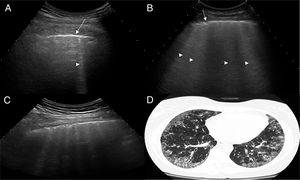

Interpretación del ultrasonidoEl hallazgo elemental a evaluar por US es la línea B, que se define como un artefacto de reverberación de base estrecha hiperecoica, que se extiende como un rayo láser hasta el borde de la pantalla. Estas líneas B por lo general no están presentes en pulmones de sujetos sanos16,17 (fig. 1). En cada espacio intercostal (EI) se registró el número de líneas B, posteriormente se registró y clasificó la suma total de todas las líneas B encontradas por el US pulmonar con base en la escala semicuantitativa propuesta anteriormente (0=normal, ≤5 líneas B; 1=leve, ≥6 y ≤15 líneas B; 2=moderada, ≤16 y ≥30 líneas B; 3=grave, ≥30 líneas B). Lo anterior con el objetivo de correlacionarse con los hallazgos de la TACAR.

ResultadosUn total de 77 pacientes con diagnóstico de ES fueron remitidos para ser incluidos en el estudio. Ningún paciente presentó, en la fase de reclutamiento, sospecha alguna de hipertensión pulmonar. Nueve pacientes fueron excluidos, ya que presentaron al menos un criterio de exclusión. El estudio finalmente se realizó en 68 pacientes con ES y 68 controles sanos. Un total de 952 EI en 68 pacientes con ES fueron examinados por US pulmonar. Las características demográficas y clínicas de la población de estudio se ilustran en la tabla 1. Veintiocho de los 68 pacientes (41,2%) mostraron signos de EPI por US en contraste con los controles sanos (4,8%) (p=0,0001). La figura 2 muestra diferentes cuadros de EPI detectados por US, incluyendo un cuadro de comparación entre US y TACAR.

Exámenes de US que muestran diferentes cuadros de EPI basados en el número de lineas B.

A. Solo hay una línea B (punta de flecha). B. Se distinguen 4 líneas B (puntas de flecha). Ambos casos presentan irregularidad pleural (flechas). C. Examen de US mostrando un espacio intercostal con 6 líneas B y neta irregularidad de la pleura en comparación con el cuadro TACAR de EPI (D).